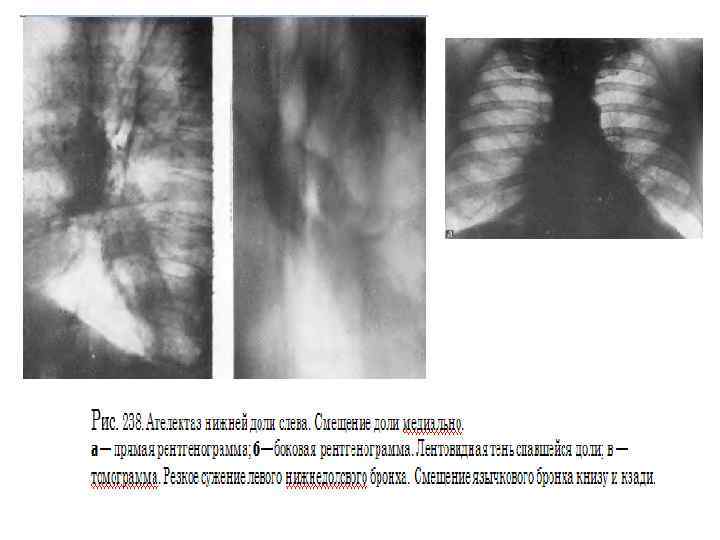

Ателектаз развивается при полной обтурации бронха опухолью, характеризуется полным рассасыванием воздуха из легочной ткани и резким ее объемным уменьшением. Кроме этих прямых признаков, как и при дистелектазе, большое диагностическое значение имеют вторичные симптомы, в той или иной степени сопутствующие ателектазу. Это, в первую очередь, смещение междолевой плевры и ее вогнутость в сторону объемного уменьшения. Выявляются также смещение корня легкого к ателектазу, средостения в сторону поражения, подъем купола диафрагмы и сужение межреберий на больной стороне, викарная эмфизема прилежащих участков легкого. Эти признаки также неспецифичны и указывают на объемное уменьшение легкого. В ателектазе также часто развиваются воспалительные и деструктивные изменения. Диагностировать их не всегда удается, лишь в отдельных случаях развиваются полости с газом и уровнями жидкости. Признаком тяжелой, обширной гнойной деструкции в ателектазе является нормальный размер доли или даже ее объемное увеличение такие случаи требуют неотложной хирургической помощи. При формировании ателектазов сегментов, долей соблюдаются определенные правила, знание которых облегчает топическую ориентировку и сокращает диагностический поиск. Во первых, любой ателектазированный участок смещается медиально и обязательно связан с корнем легкого. Во вторых, тень ателектаза смещается туда, где в норме располагались до этого сегмент или доля. В третьих, все доли и сегменты, граничащие с междолевой плеврой, в определенных проекциях обязательно сохраняют четкость очертаний. Участки же, не соприкасающиеся с плеврой, в любой проекции имеют размытый контур. Кроме медиального направления, доли спадаются следующим образом:

справа верхняя вверх и вперед, средняя вперед, нижняя вниз и кзади; слева верхняя вперед, нижняя вниз и кзади. Напомним сегменты, граничащие с междолевой плеврой: справа в верхней доле S 2 и S 3 , нижней S 6, S 7, S 8, слева в верхней S 1 2, S 4 и S 5, нижней S 6 и S 8. Оба сегмента средней доли ограничены междолевой плеврой. При формировании ателектазов междолевая плевра часто значительно изменяет свое положение и выявляется в проекциях, перпендикулярных тем, в которых она видна в норме. Например, при ателектазе средней доли горизонтальная междолевая плевра прослеживается только в боковой проекции, при ателектазе S 6 с обеих сторон (особенно часто слева) косая междолевая плевра отчетливо видна в прямой проекции. Сочетание ателектазированных долей и сегментов указывает на пораженный бронх, но не всегда эта зависимость соблюдается в полной мере. При резком стенозировании просвета бронха может не быть признаков нарушения вентиляции ткани легкого. И наоборот, при четко видимом просвете может сформироваться дистелектаз паренхимы. Такой вариант особенно характерен для рака Б 1 2 слева, часто имеющего перибронхиальный стелющийся рост и сопровождаемого симптомом "удлинения бронха".

Некоторые виды ателектазов носят "скрытый" характер и для их выявления требуется внимательность, опыт и соблюдение методик обследования. В первую очередь, это ателектаз нижней доли слева, который "прячется" ретрокардиально и проявляется в прямой проекции лишь дополнительным паракардиальным контуром. Не видна порой в прямой проекции ателектазированная средняя доля, зато не заметить ее на боковом снимке невозможно. Бывают случаи, когда на фоне ателектаза, дистелектаза или обтурационной пневмонии определяются просветы мелких бронхов на большом протяжении. Выявление такой воздушной бронхограммы может быть причиной роковой диагностической ошибки. Этот симптом считается патогномоничным для воспалительных процессов в легких, особенно популярен при КТ диагностике. Однако для воспалительных процессов неукоснительно соблюдается следующее правило воздушная бронхограмма должна быть прослежена на всем протяжении, от главного, долевого бронхов до мелких ветвей. Если есть участки прерывания просвета бронхов, то в первую очередь следует думать о центральном раке. Полный ателектаз доли, легкого часто не позволяет определить истинные размеры опухолевого узла в корне. В силу их одинаковой плотности даже КТ без контрастирования не поможет в таких случаях, и лишь КТ с болюсным усилением иногда может дать возможность дифференцировать ателектаз от опухоли. На фоне ателектаза не следует пытаться искать очертания опухоли или лимфоузлов, так как истинные контуры в легких формируются не границе двух тканей воздушной и безвоздушной (то есть мягкотканной плотности).

Применение функциональных проб позволяет заметить смещение средостения в фазе выдоха в противоположную сторону. Анализ легочного рисунка в этой фазе показывает, что соответственно пораженным участкам заметно обеднение сосудистого рисунка из за веерообразного раздвигания сосудистых ветвей и уменьшения кровенаполнения, вследствие повышенного внутриальвеолярного давления. По мере роста опухоли наступает четвертая фаза. Последняя связана с полным перекрытием просвета бронха, чему способствует скопление в нем слизи, мокроты и крови. Все эти факторы рано или поздно приводят к III стадии нарушения бронхиальной проходимости, к возникновению ателектаза (рис. 229). Именно сложный характер пробки, обтурирующей бронх, является одной из причин так называемых перемежающихся ателектазов. Стадия ателектаза обычно диагностируется при поражении зональных и долевых бронхов и реже при сегментарных. Сегментарные поражения часто расцениваются как проявления пневмонии, и лишь тогда, когда развивается ателектаз зоны или доли, устанавливается диагноз рака легкого. Описанные фазы нарушения бронхиальной проходимости от гиповентиляции через клапанное вздутие к ателектазу также последовательно наступают и при развитии опухоли в зональных долевых и главных бронхах.

Рис 229. Ателектаз переднего сегмента верхней доли слева. а — прямая рентгенограмма; 6 — боковая томограмма. Сужение устья переднесегментарного бронха.